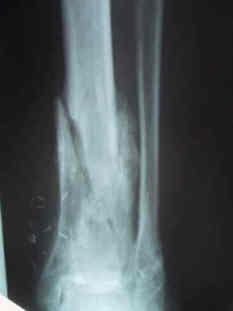

Radiographs

findings

- often shows a lytic region surrounded by an area of sclerosis

- may mimic a neoplastic processes

- bone loss must be 30-40% before evident on plain films

- sequestrum: devitalized bone that serves as a nidus for infection

- involucrum: formation of new bone around an area of bony necrosis